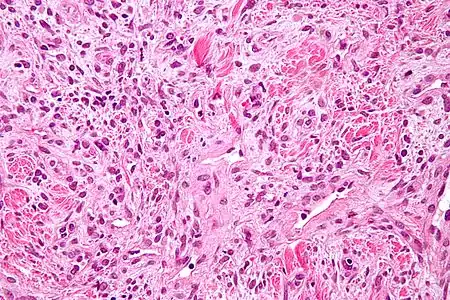

Les tumeurs fibreuses solitaires sont constituées de cellules mésenchymateuses, de différenciation fibroblastique[6]. Elles sont ovoïdes ou fusiformes. Leur cytoplasme est riche en collagène[3]. L'architecture tissulaire est hétérogène, supportée par un tissu conjonctif collagénique et alterne entre des zones bien fournies en cellules et des zones plus pauvres, où l'espace intercellulaire est plus riche en acide hyaluronique[3].

L'immunohistochimie retrouve l'antigène CD34 dans 80 % des cas[30], ce qui permet de différencier les tumeurs fibreuses solitaires des mésothéliomes[3]. Les tumeurs expriment également la vimentine, mais aucune des cytokératines[30].

Aspect en microscopie optique (coloration H&E).